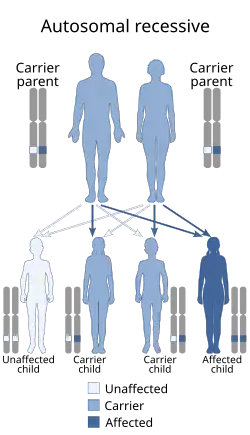

Waardenburg syndrome is caused by mutations in any of several genes that affect the operation of neural crest cells in embryonic development. Most types of Waardenburg syndrome are caused by autosomal dominant mutations. The few that are autosomal recessive are rare. In most cases, an affected person has inherited it from one parent with one of the dominant forms of the condition. A small percentage of cases result from spontaneous new mutations in the gene, where no family history of the condition exists.

- Type 3 is caused by a mutation in the gene PAX3, the same gene as in type 1.[2] It can be inherited in an autosomal dominant or autosomal recessive manner; it is possible for two parents with Waardenburg syndrome type 1 to have a child carrying both mutated copies of the PAX3 gene (25% chance) and present with Waardenburg syndrome type 3. A missense mutation has been documented to have this effect. However, it is also possible for Waardenburg syndrome type 3 to present spontaneously with just one mutated copy of PAX3. A deletion of the paired domain region of the gene has been documented to have this effect.[26][5] However, no major correlation has been found between type of mutation and disease severity. Severity tends to be dictated by mutations in other genes (epistasis), as evidenced by distinct familial patterns in severity not tied to Waardenburg mutation type.[5] Mutations in both copies of PAX3 have sometimes led to death before or shortly after birth, and mice with loss-of-function mutations in both copies of the gene do not survive.[5]